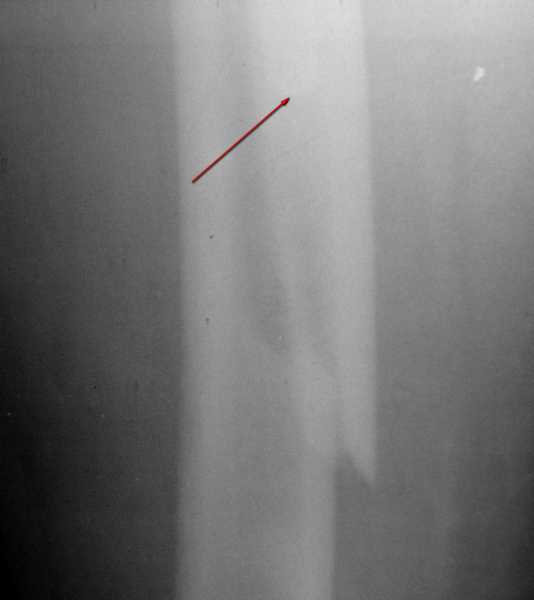

Вот фрагменты этих снимков с более различимыми областями интереса.

Видимо, тут надо добиваться точной репозиции этой спирали вдоль протеза, чтобы воссоздать ложе для ножки.